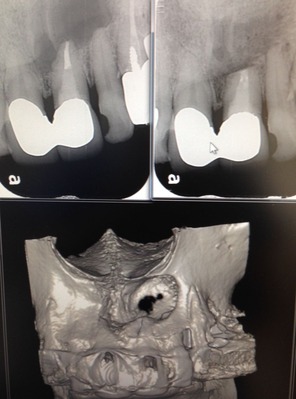

レントゲンで根の先が黒くなり、

膿んで骨がとけて、

ここに穴が開いてますね!

細菌が根の先にまで 進入してくると、

骨の細胞は細菌と戦えないんです。

一旦、骨がとけて肉芽って呼ぶ炎症性のお肉に変わります。

こんなに大きな穴でも、治ります。

少し根っ子を削るので、短くはなりますが。